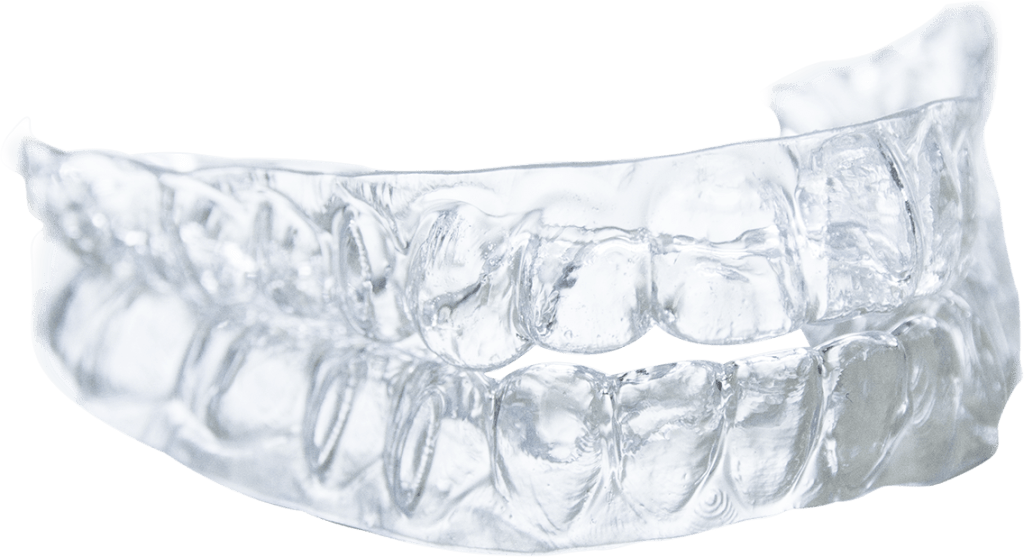

Oral appliance therapy (occlusal splints / night guards)

A custom-made splint (sometimes called a night guard or occlusal guard) is often the first line of defence. It:

- Protects teeth from direct contact

- Reduces wear and attrition

- Can relieve muscle strain

Occlusal splints are designed by your dentist to fit your bite and are usually worn at night. amrdental.com.au

Types include:

- Hard acrylic splints — durable, often used for moderate to severe bruxism

- Soft thermoplastic splints — more comfortable and may improve compliance

Soft splints fitted properly often have high retention and patient comfort. noordinarydentistry.com